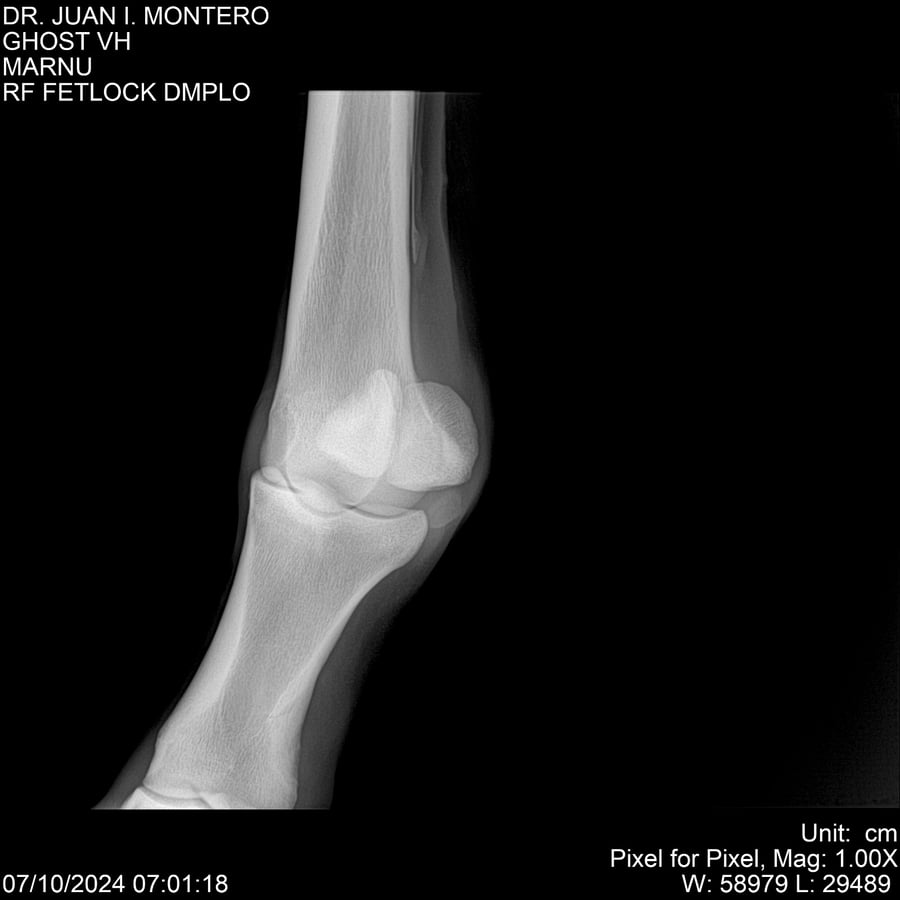

LOTE 15, GHOST VH 🔥 🔥 🔥 Lote Anterior Volver al remate Lote Siguiente Ficha Contacto Montevideo - Ficha del Lote Identificador: #282525 Categoría: Yeguarizos Montevideo - 69 Visualizaciones ClicData Contacto Empresa: Abelenda N. R., Walter Hugo Nombre*: Teléfono* : E-mail* : Mensaje Enviar Registrese gratis Este contenido Exclusivo está disponible sólo para usuarios registrados Ingresar